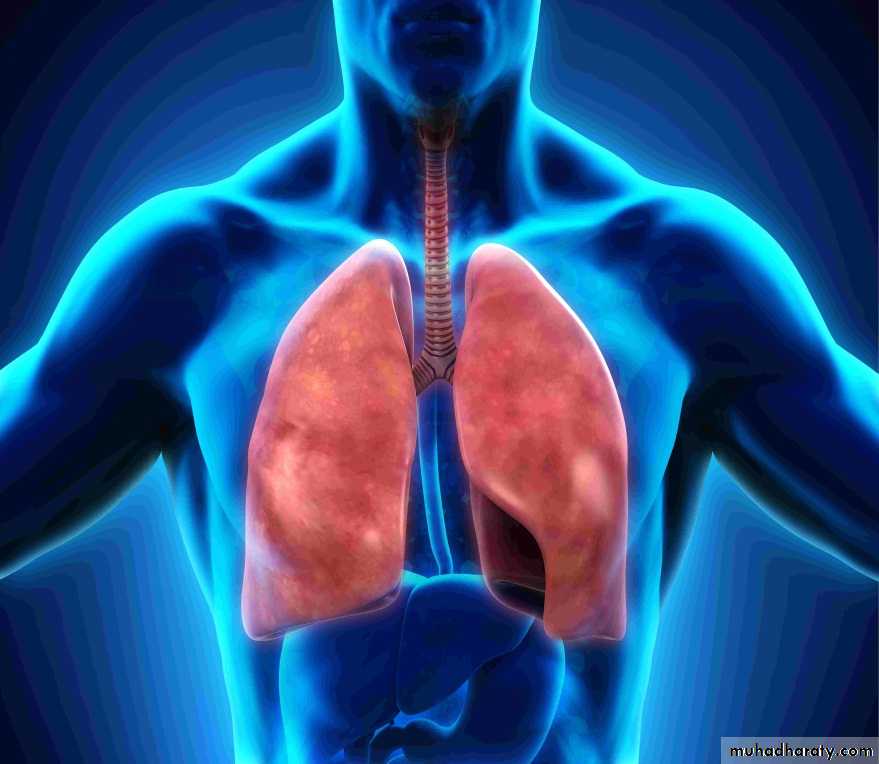

Combining form for Body SystemsRespiratory

• alveol/o alveolar• bronch/o bronchial tube

• cyan/o blue

• laryng/o larynx

• nas/o nose

• rhin/o nose

• pharyng/o pharynx

• phren/o diaphragm

• pneumon/o lung

• tonsill/o tonsils

• trache/o trachea